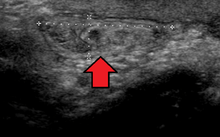

In the diagnosis of abdominal hernias, imaging is the principal means of detecting internal diaphragmatic and other nonpalpable or unsuspected hernias. Multidetector CT (MDCT) can show with precision the anatomic site of the hernia sac, the contents of the sac, and any complications. MDCT also offers clear detail of the abdominal wall allowing wall hernias to be identified accurately.[8]